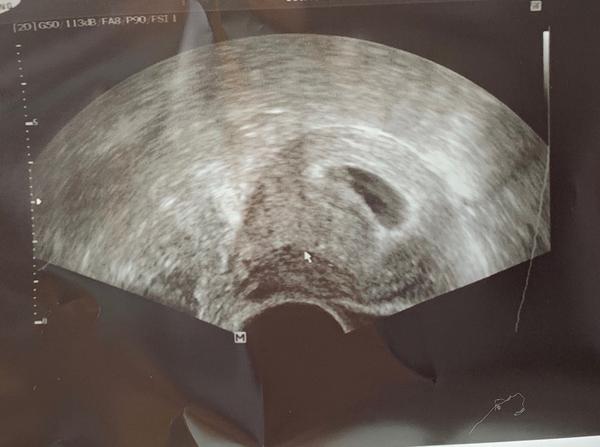

Snímek z ultrazvuku v 6+2: Má smysl žádat o fotku?

Já mám fotku z ultrazvuku 6+2 nebo 6+4, už si přesně nepamatuju,a byla tam malá už hezky vidět. Dokonce to vypadalo jako by mávala ručičkou 😄

V 6+2 bude vidět tak nějaká tečka. Já mám celkem hezky obrazek z 9tt, tak bys mohla s fotkou vydržet do další kontroly.

@klokanka31 tak vidíš tady ty obrázky ne? Je to takové černá skvrna a srdíčko je ještě menší tečka v te skvrně :D to ani není vidět na obrázku, jen na lepším utz je vidět jak se to tam hýbe.

Já měla v 6+2 jen gestační váček, ale fotku mi udělal. Vypadá to jako malá kapička 😊